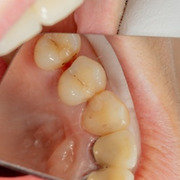

치과에서 치료 안 하는 충치가 있다? '정지우식'이란? 작성자Snoopy|작성시간20.02.08|조회수207 목록 댓글 2 글자크기 작게가 글자크기 크게가 치과에서 치료 안 하는 충치가 있다? '정지우식'이란?아무리 닦아도 지워지지 않고, 너무나 선명히 보이는 충치.까만 충치가 신경 쓰여 치과에 갔는데 이리저리 살펴보던 치과의사가 말하길 “치료는 할 필요 없고 칫솔질과 치실로 관리만 잘해주면 된다”고 한다. 너무 정직한 의사인지, 치료할 줄 모르는 의사인지... 반신반의했던 당신이라면 “정지우식”이라는 말을 잘 알아둘 필요가 있다. ◇ 치료가 필요 없는news.v.daum.net 다음검색 현재 게시글 추가 기능 열기 북마크 공유하기 신고 센터로 신고 댓글 댓글 2 댓글쓰기 답글쓰기 댓글 리스트 작성자계정혜 | 작성시간 20.02.08 그렇군요 작성자청명 | 작성시간 20.02.09 이상하게 치과만 가면 계속해서 할꺼리가 생기는 이상한 현상 ㅠㅠ안갈수도 없고, 갈수도 없는 치과! 댓글 전체보기